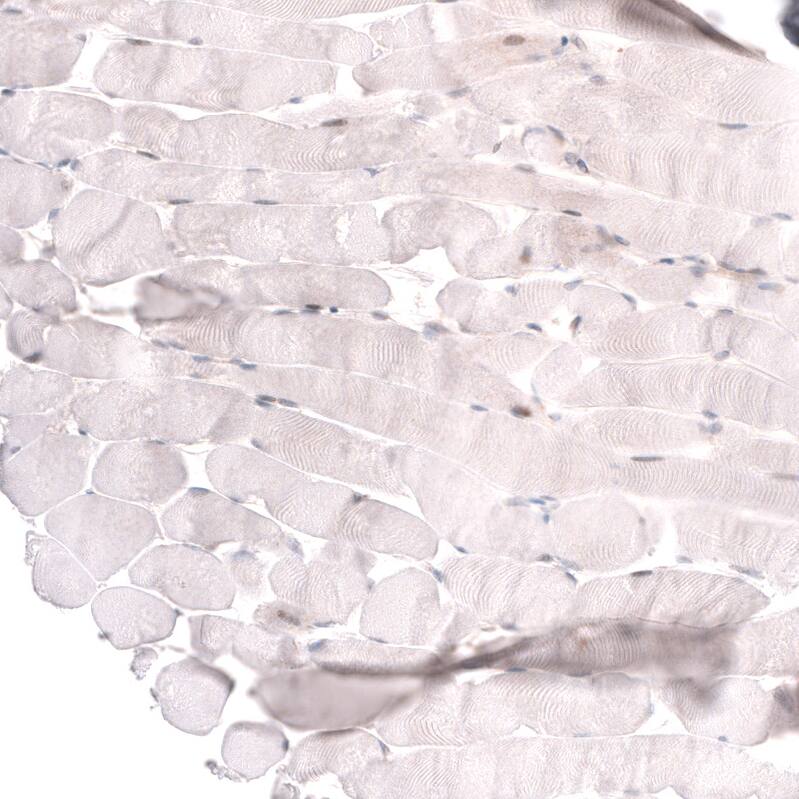

Immunohistochemistry-Paraffin: ADAM10 Antibody [NBP3-43825]

Analysis in human prostate and skeletal muscle tissues using NBP3-43825 antibody. Corresponding ADAM10 RNA-seq data are presented for the same tissues.